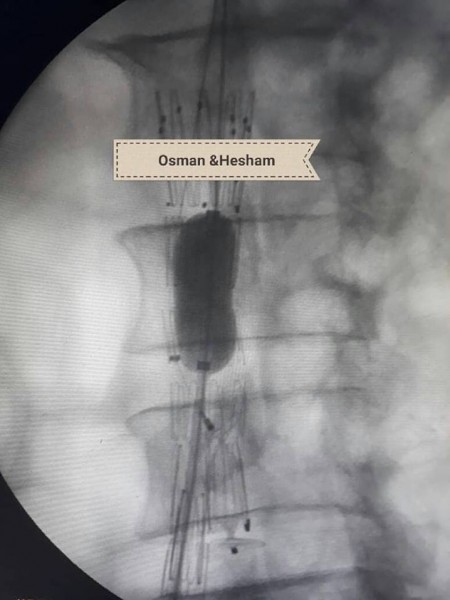

وحول خطوات الجراحة أضاف الدكتور عثمان انه فور إجراء أشعه الدوبلكس للمريض على للشريان الحرقفى الأيسر والشريان الأورطى تبين وجود تمدد ووجود قرحه نشطة بالشريان مع تصلبات شديدة غير مستقرة وانسداد بالدعامة السابقة وكذلك تم إجراء أشعه مقطعية على الشريان الأورطى والطرفين بالصبغة والتي أكدت نفس النتائج ، فكان القرار استخدام دعامات مغطاة للشريان الأورطى والشريان الحرقفى الأيمن وذلك نظراً لأن الوضع الصحي للمريض لا يسمح بإجراء تدخلات جراحية للشريان الأورطى ، ثم تم عمل زرع شريان من الطرف الأيمن للطرف الأيسر لصعوبة شق الدعامة السابقة لاختلاف كبير فى المقاسات التي تم تركيبها للمريض فى وقت سابق .

ومن جانبه أضاف الدكتور هشام أبو العيون مدرس جراحة الأوعية أن تلك الحالة ثالث حاله ايفار EVAR فى صعيد مصر وأول حالة يستخدم بها Aorto-uniiliac system والتي تمت بنجاح منقطع النظير ،وخرج المريض بنبض محسوس بالطرفين وغادر العناية بعد 24 ساعة فى صحة جيدة ودون حدوث اى مضاعفات ، مشيراً أن ذلك تم بفضل جهود الفريق الطبي للعملية والذى تكون من الدكتور محمد جمال مدرس مساعد جراحة الاوعية الدموية إلى جانب فريق التخدير بقياده الدكتور ايمن ممدوح الأستاذ بقسم التخدير والعناية المركزة ، وكذلك أطقم التمريض بالعمليات والعناية المركزة.